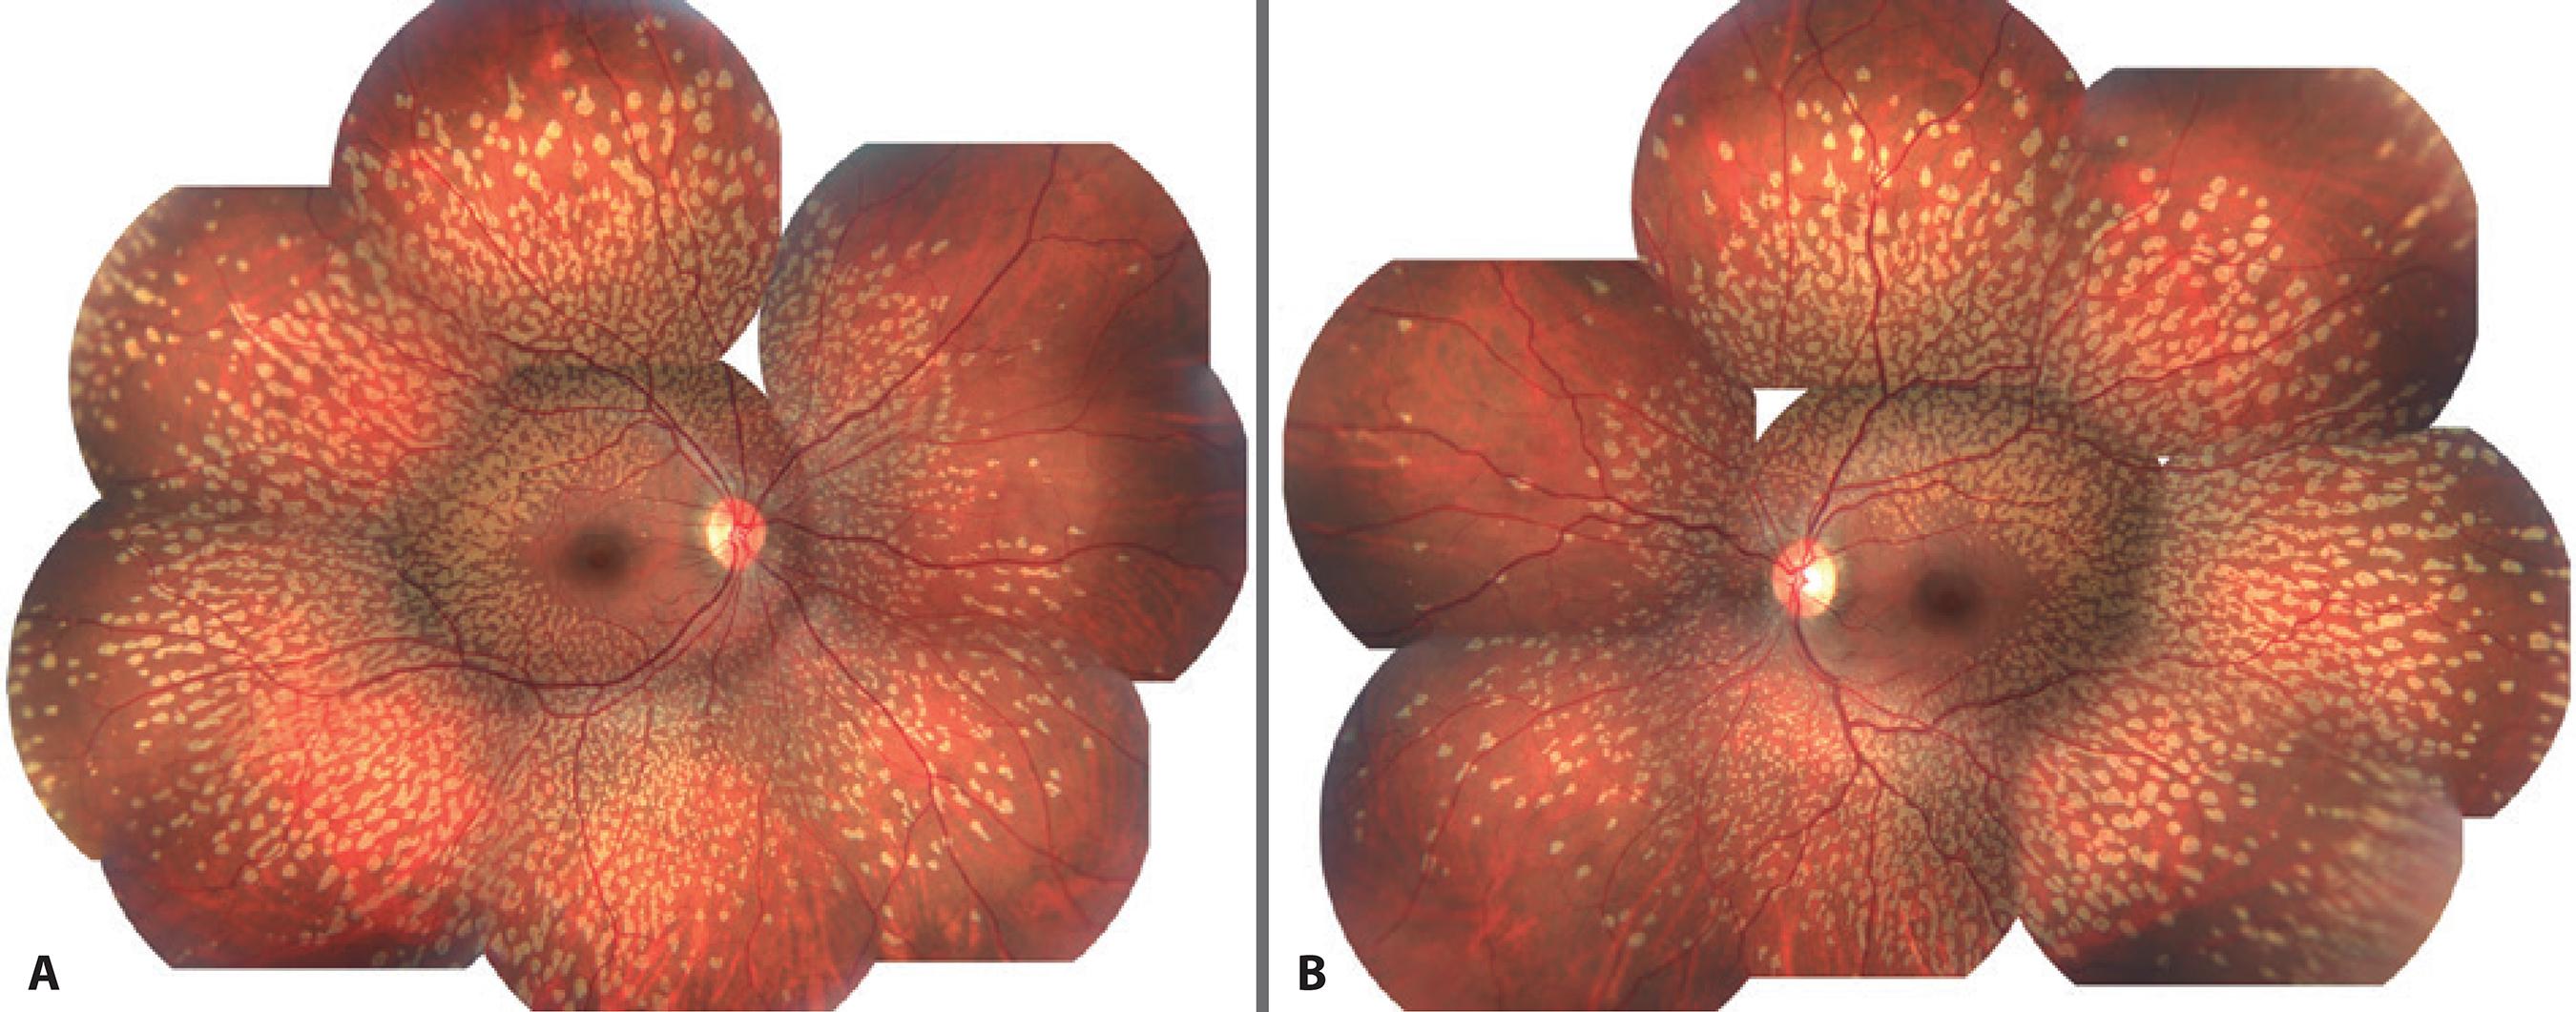

A 27-year-old woman was referred for a regular ophthalmic examination. Her visual acuity was 20/20 OU and there were no abnormalities in slit-lamp biomicroscopy. Fundus photographs in both eyes displayed multiple, small, bilateral, symmetrical retinal flecks that affected the post-equatorial retina but spared the macular region (Figure 1). No family members were affected, and there was no history of consanguinity between the parents.

Figure 1 A and B) Fundus photographs showing numerous yellowish flecks that affected the post-equatorial retina but spared the macula.